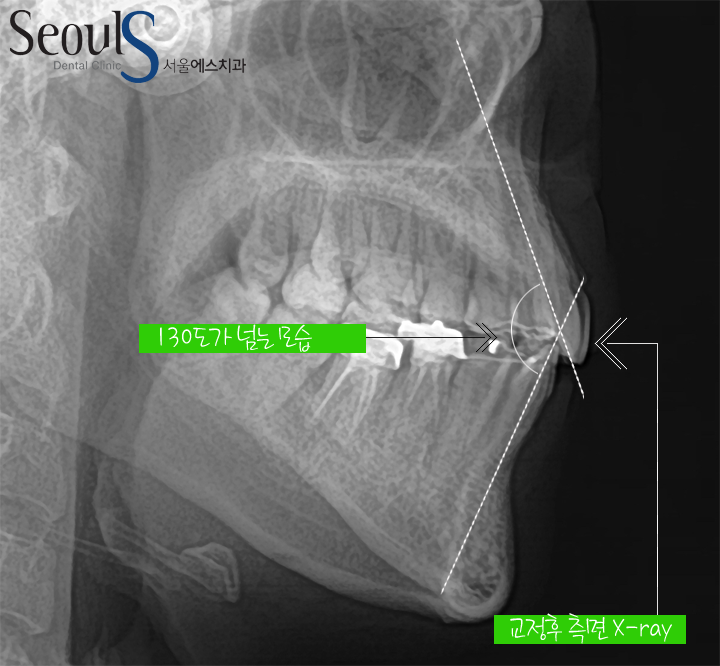

교정후 측면 X-ray모습으로

튀어나왔던 앞니가 쏙~~~ 들어갔고

교정전 아래위 앞니의 각도가 90도에 가까왔는데 교정후 정상 각도로 개선된 모습입니다

교정 전후 측면 X-ray 모습입니다

치아 돌출이 개선된 모습입니다